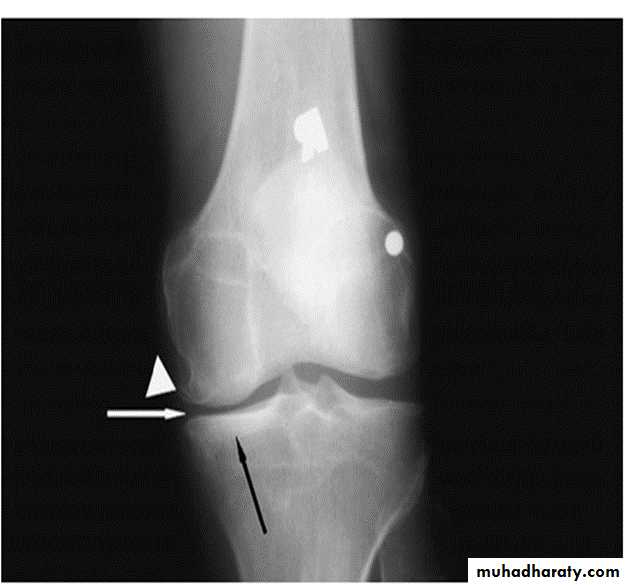

Radiographic features:

Five hallmarks:

* Narrowing of joint space, usually asymmetrical

*Subchondral sclerosis

* Subchondral cysts (true cysts or pseudocysts)

* Osteophytes

* Lack of osteoporosis